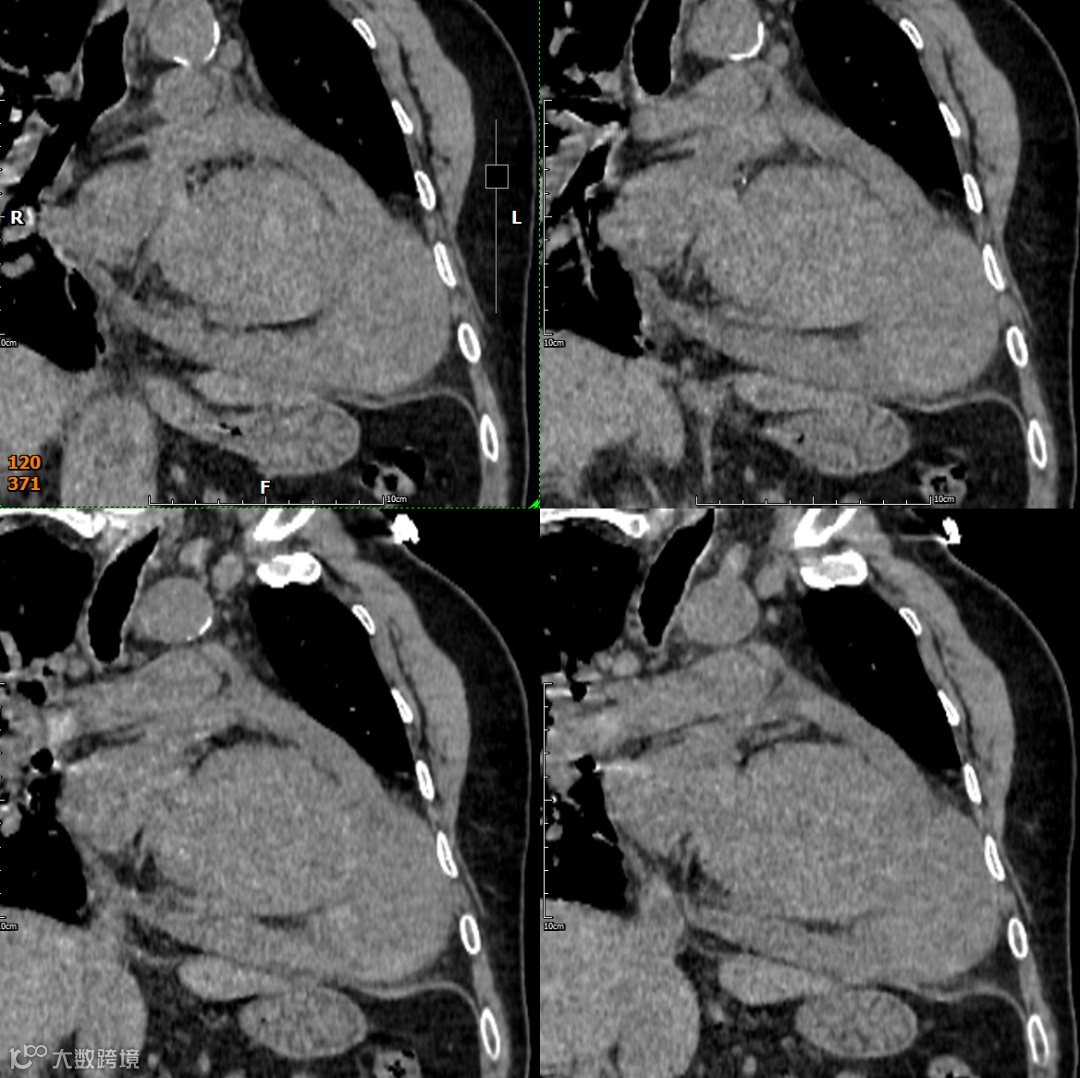

影像学检查

手术记录:纵劈胸骨正中开胸,悬吊心包,见左室明显增大,心尖部假性室壁瘤形成,大小约10cm×6cm,并与左侧心包粘连,分离室壁瘤粘连,切开假性室壁瘤见左室壁破口约8cm,切除室壁瘤体坏死变薄心肌组织

形态与位置:与左心室腔相邻的囊状、球状或葫芦状对比剂充盈腔。特征性的窄瘤颈是其关键。位置常在心包反折附近(下壁、后壁、侧壁)。

瘤壁:菲薄,无心肌密度!主要由心包(可能钙化)和血栓(不强化或延迟强化)构成。

瘤颈:清晰可见的、狭窄的开口(如瓶颈状)将假性瘤腔与左心室腔相连。破口处心室壁中断是直接征象。

腔内:可见对比剂充盈,内常有血栓(充盈缺损)。

心包:局部心包增厚、粘连、积液常见。瘤体常部分嵌入心包内。

多平面重建(MPR)与三维重建(3D): 对于清晰显示瘤颈的形态、大小、位置以及与左心室壁的关系至关重要。